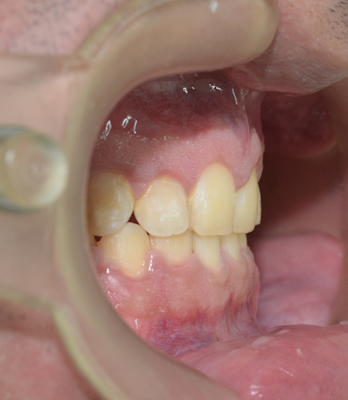

Caso de corrección de apiñamiento con ortodoncia fija

Paciente femenino de 13 años de edad, acude a consulta por dientes desalineados en la zona frontal, buscando mejorar la estética de su sonrisa y facilitar la higiene dental.

Se colocó ortodoncia fija con brackets metálicos, iniciando la fase de alineación y nivelación. El tratamiento incluye arco ortodóncico para corrección progresiva, ligadura metálica para control de movimientos dentales, y ajustes periódicos para guiar la posición dental.

La paciente en fase inicial de tratamiento

En la evaluación clínica se observaron:

- Apiñamiento anterior superior

- Rotaciones dentales en incisivos laterales

- Desalineación en el sector estético (zona visible al sonreír)

- Relación oclusal susceptible de mejora